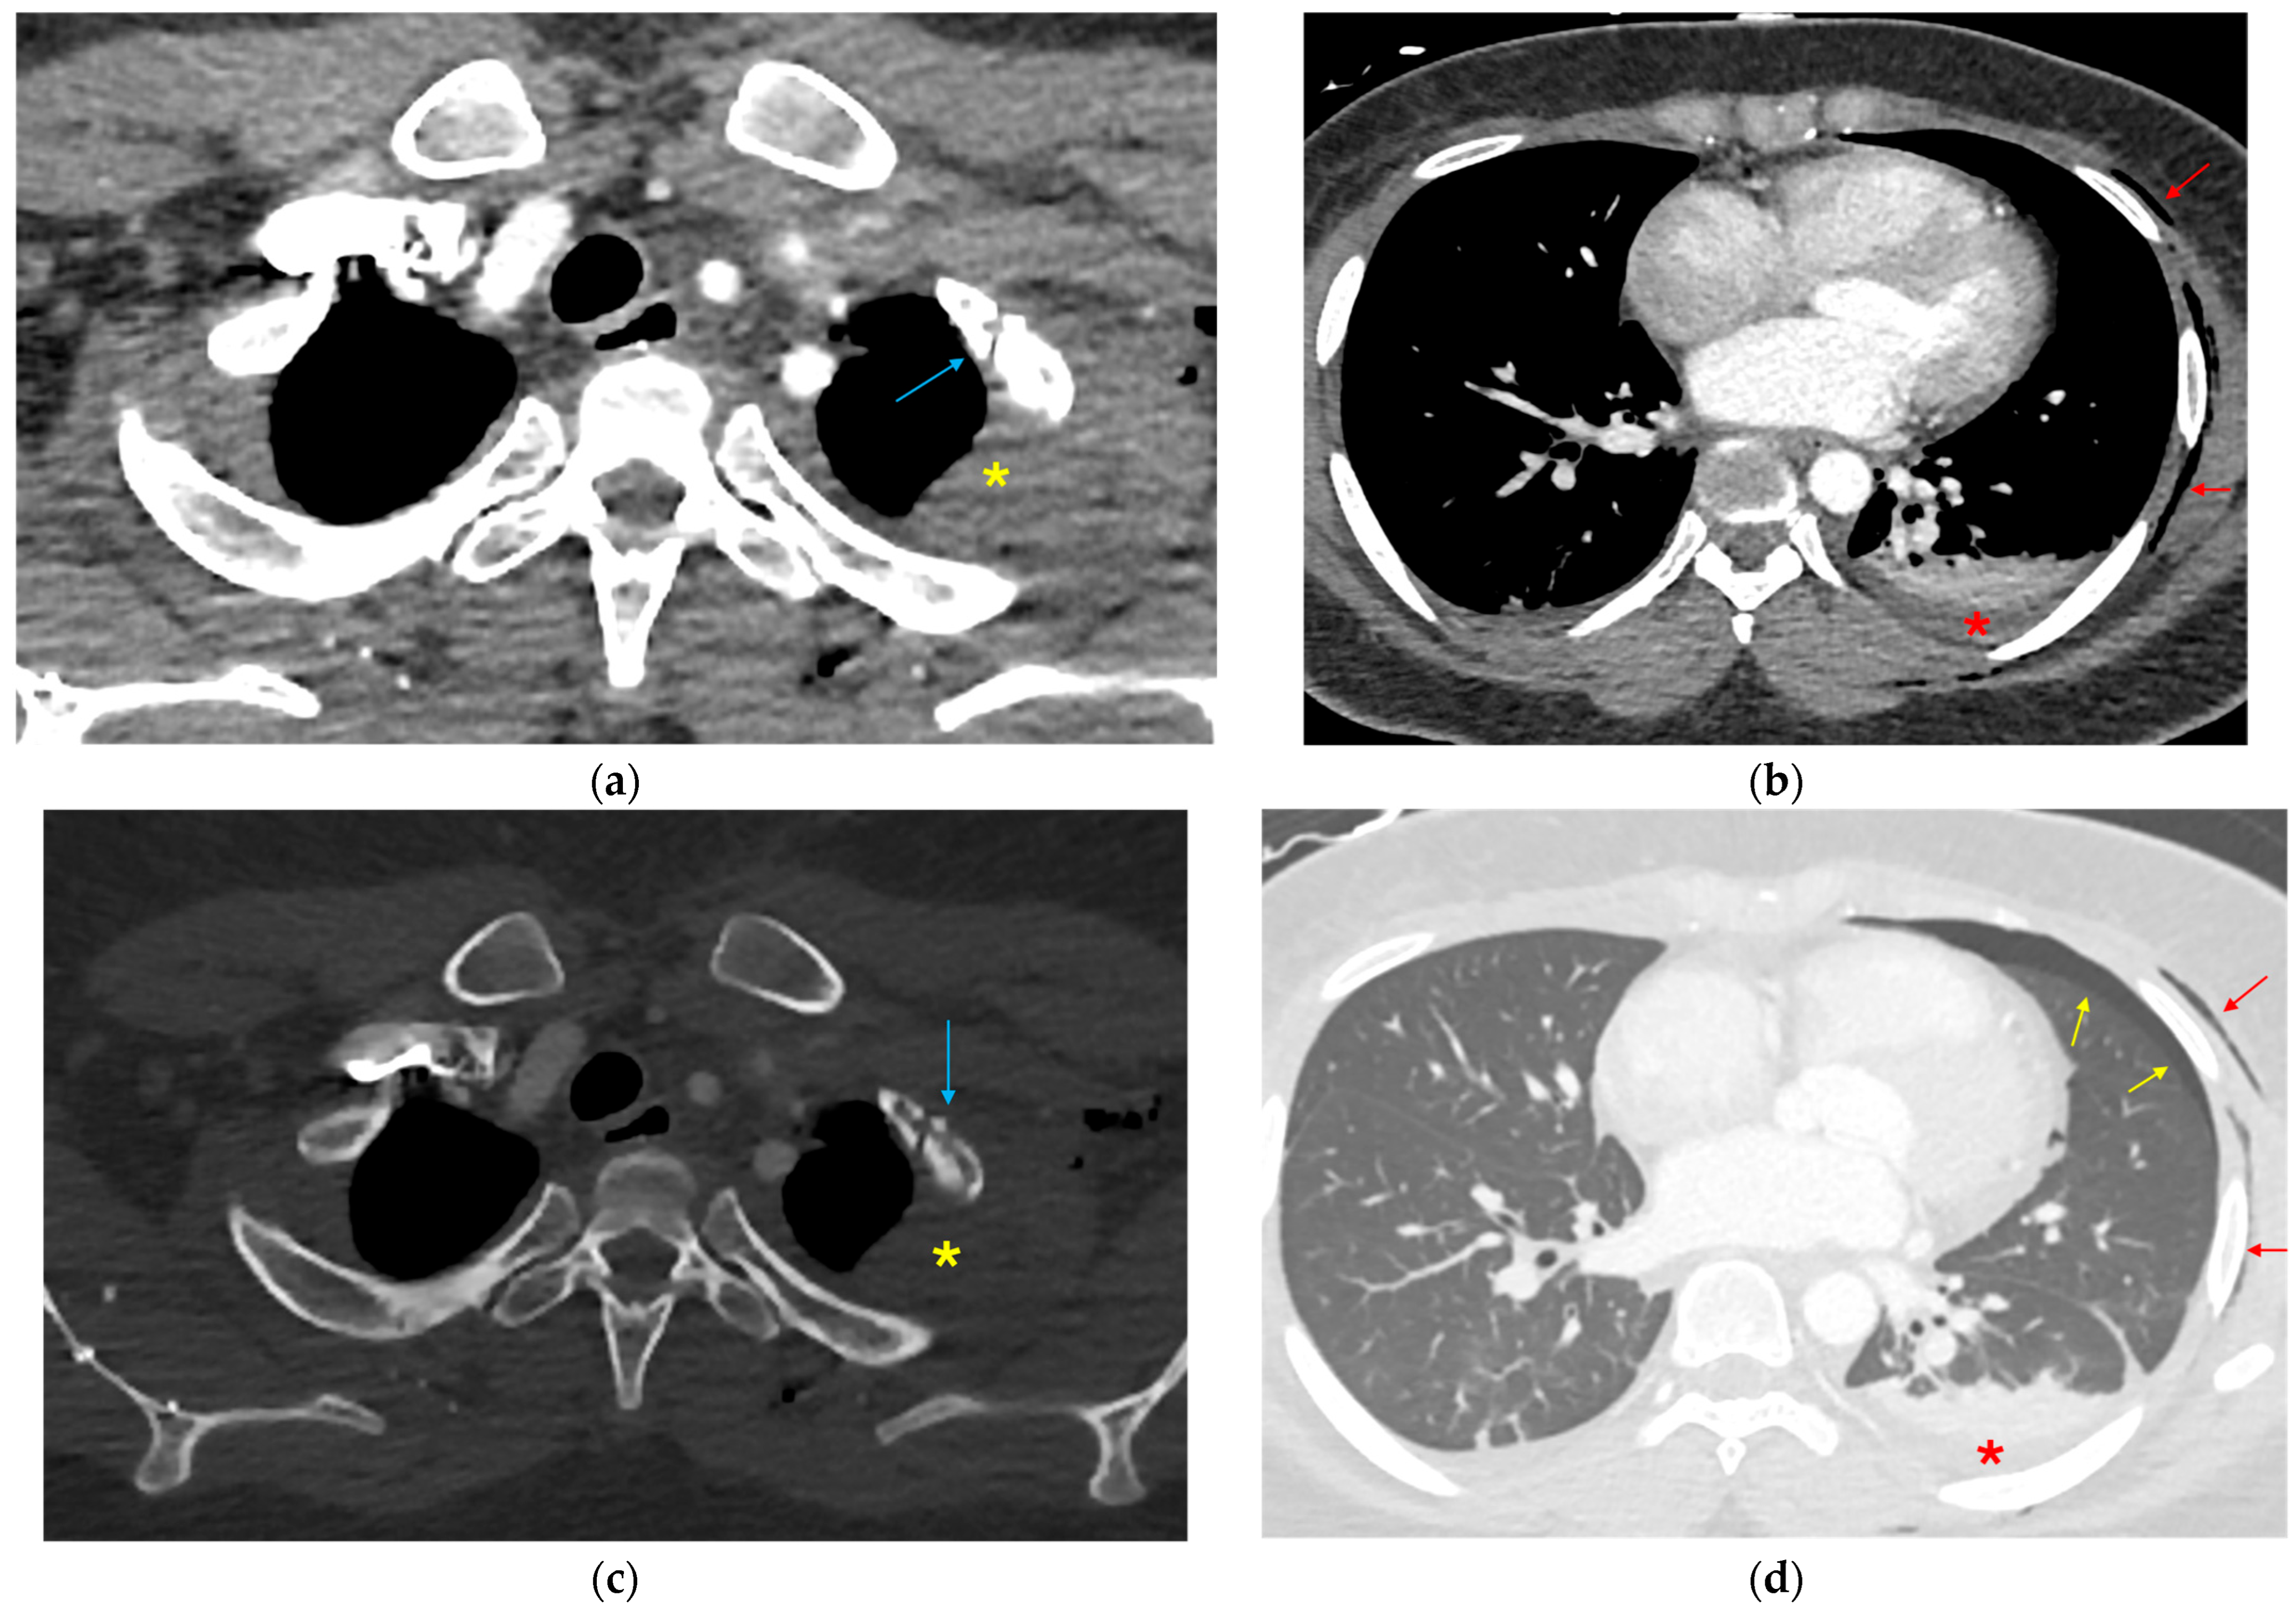

3.1.1. Direct Signs of Aortic Injury

3.1.2. Indirect Signs of Aortic Injury

3.1.3. Mimics and Anatomic Variations